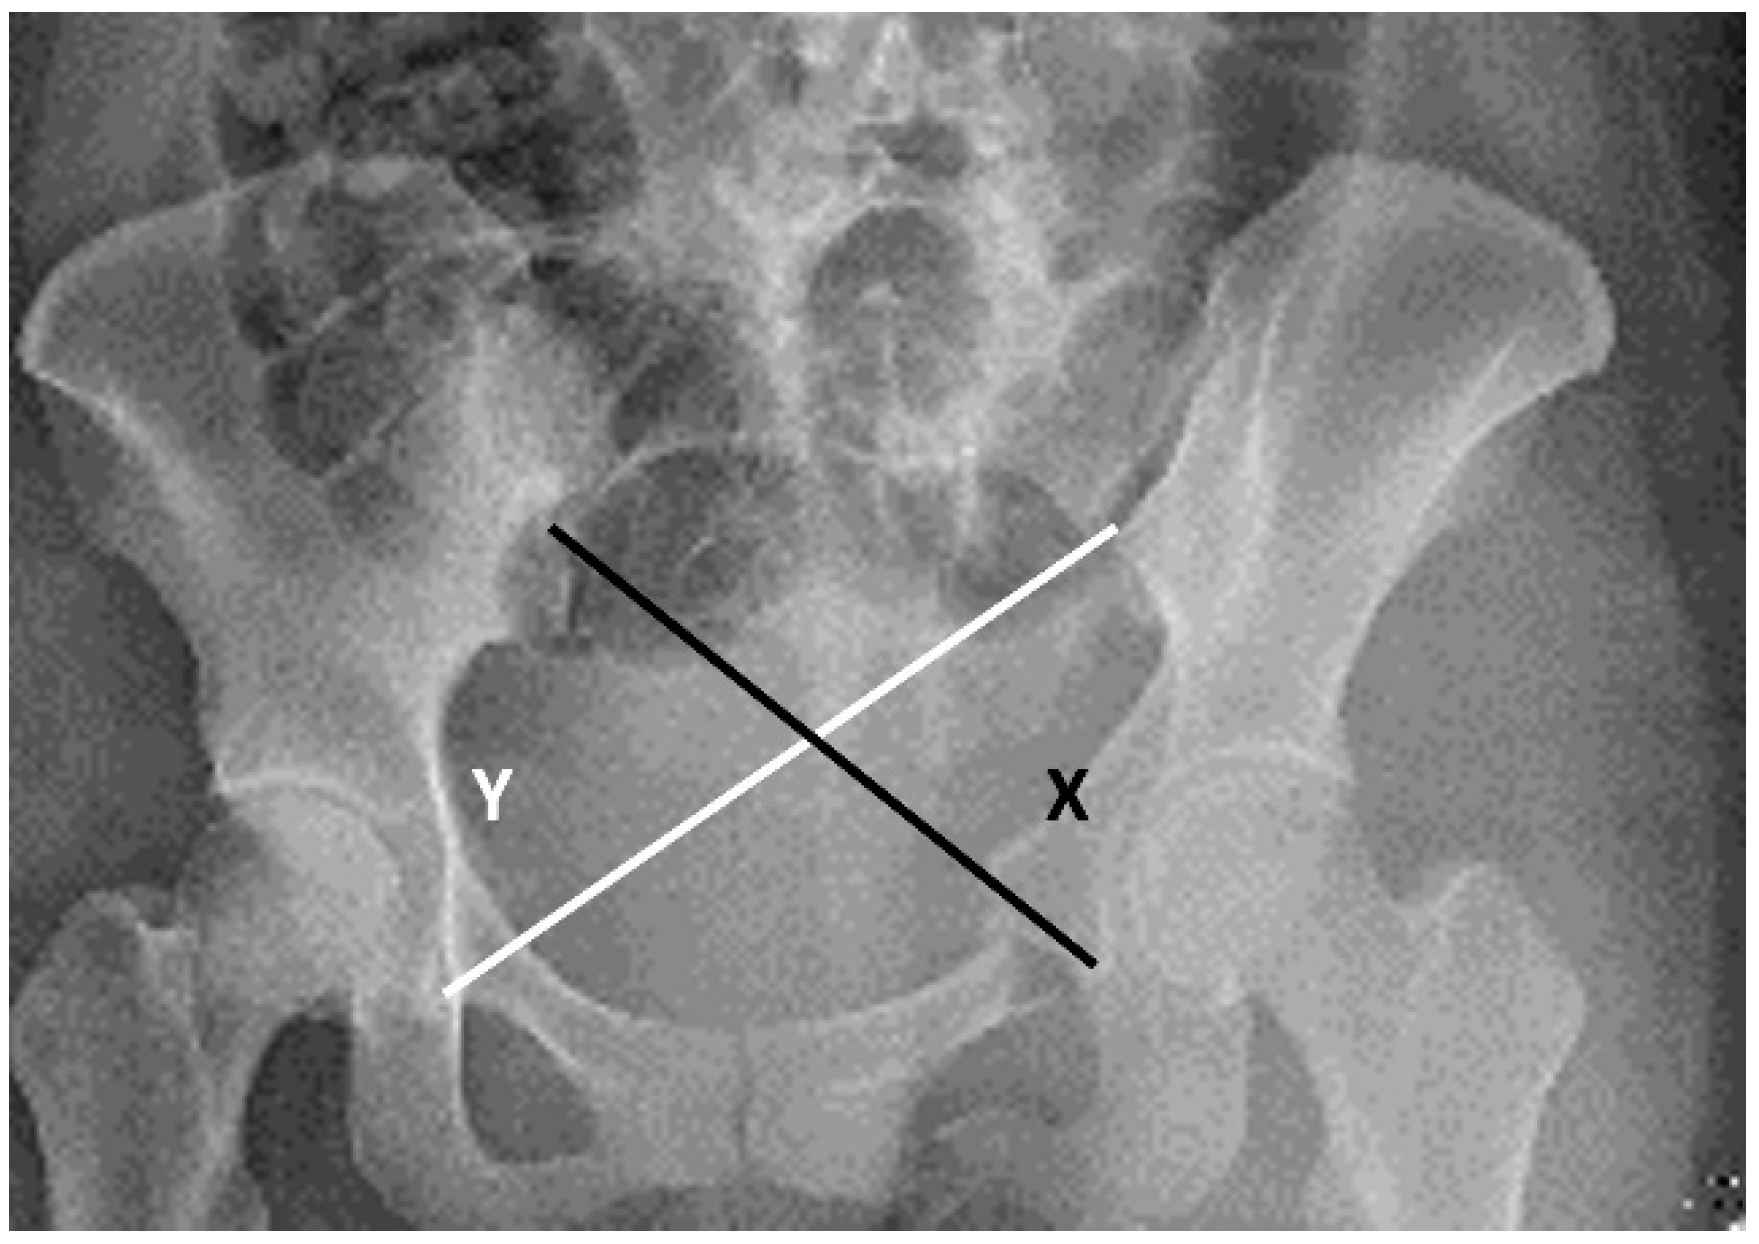

| Keshishyan et al., 1995 | Cross measurement method (Keshishyan Method) [14] | The measurement method described by Keshishyan et al. for assessing the displacement of pelvic ring continuity in children used only the AP pelvic view. Originally, this method was applied for skeletally immature patients and measures the distance from the inferior aspect of the sacroiliac (SI) joint to the contralateral triradiate cartilage. We used the modified method described by Lefaivre et al. to assess our adult patients. Observers were instructed to measure from the inferior SI joint (iliac side) to the inferior aspect of the teardrop in the AP pelvic view. “Y” was the length from the left SI joint to the right teardrop, and “X” was the opposite. Observers were instructed to measure the distance using the measuring software. We then calculated the ratio (X/Y) to standardize the baseline of comparison of the displacement (Figure 4). |